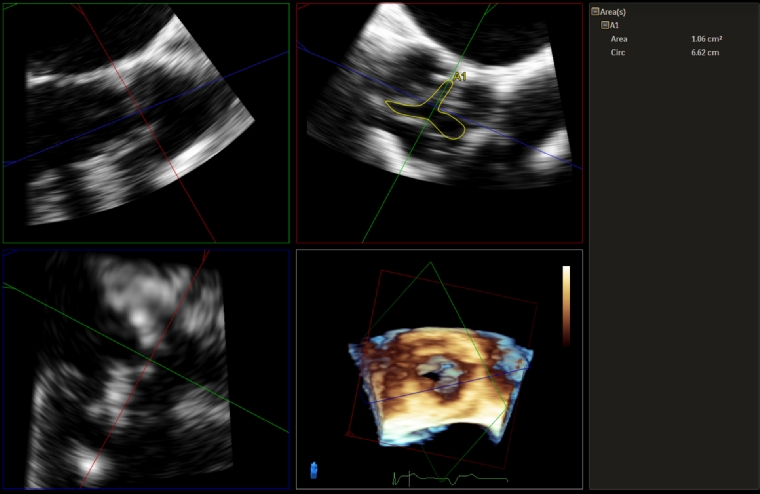

Three-dimensional (3D) echocardiography can be performed with both TTE and TOE, and the assessment of valvular heart disease is a key clinical application. The important views to acquire 3D images of the aortic valve are from the parasternal long and short axis on TTE, and mid-oesophageal long axis (120-140 degrees) and aortic valve short axis on TOE, both with and without colour [7]. Multiplanar reconstruction techniques are also available in 3D echocardiography to help with accuracy of measurements. For AS, 3D allows confirmation of AS aetiology such as calcific, degenerative or rheumatic, and clarifies both the location and extent of these pathologies. Direct planimetry of the aortic valve on 3D using multiplanar reconstruction is particularly useful (Figure 1), especially when 2D echocardiography does not provide the optimal aortic valve short-axis view. 3D TTE has high reproducibility and agreement with TOE, although this correlation is in part dependent upon the quality of 2D TOE views [8]. In addition, 3D is especially helpful in measuring the dimensions of the LVOT, which is a major potential source of error in the continuity equation calculation for aortic valve area. The suboptimal accuracy of 2D LVOT and aortic valve area measurements is a result of calculating the cross-sectional area from a single diameter and erroneously assuming that this area is circular [9]. In fact, in a recent meta-analysis, there was good correlation between the LVOT area, aortic annular area, perimeter and diameter measured on 3D TOE compared to computed tomography (CT), which is critical in assessing AS severity and preprocedural planning for TAVI [10]. Although CT has largely replaced TOE for TAVI prosthesis sizing, TOE remains an alternative strategy, especially when CT is contraindicated.